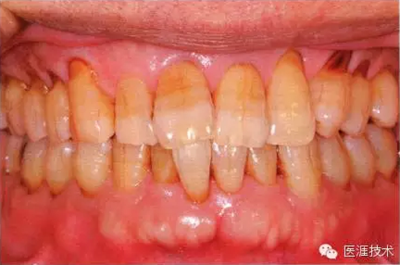

55歲牙周炎男性的臨床照片

55歲男性抽煙患者(1天20支、抽煙35年)。菌斑控制得不好。通過牙周探診,全頜有4~9mm的牙周袋,有1~3度的根分叉部病變。通過X光片觀察,上頜前牙中度牙槽骨吸收,其他地方有中度牙槽骨吸收。受吸煙影響,牙齦纖維性肥厚,呈紅黑色。牙齦幾乎沒有浮腫和發(fā)紅,所以這個病例是從外觀上無法預(yù)測病癥嚴(yán)重程度的病例。